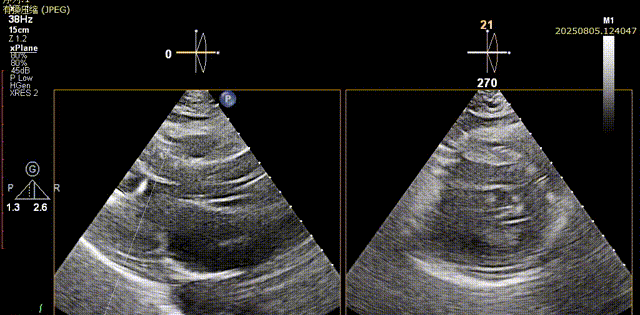

体外量取工作距离,猪尾置入窦底,交换加硬导丝,加硬导丝支撑下缓慢置入大鞘。大鞘置入后,经加硬导丝导入AL导管,采用150cm直头导丝跨瓣,超声下可见导丝顺利通过瓣口,将AL导入左室,交换预塑形加硬导丝

直头导丝跨瓣

AL导管送入左室

加硬导丝送入左室

心尖切面确认导丝位置